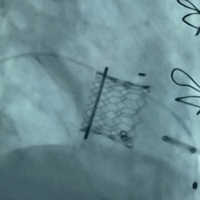

球扩瓣膜

左室术前造影

(可见大量反流)